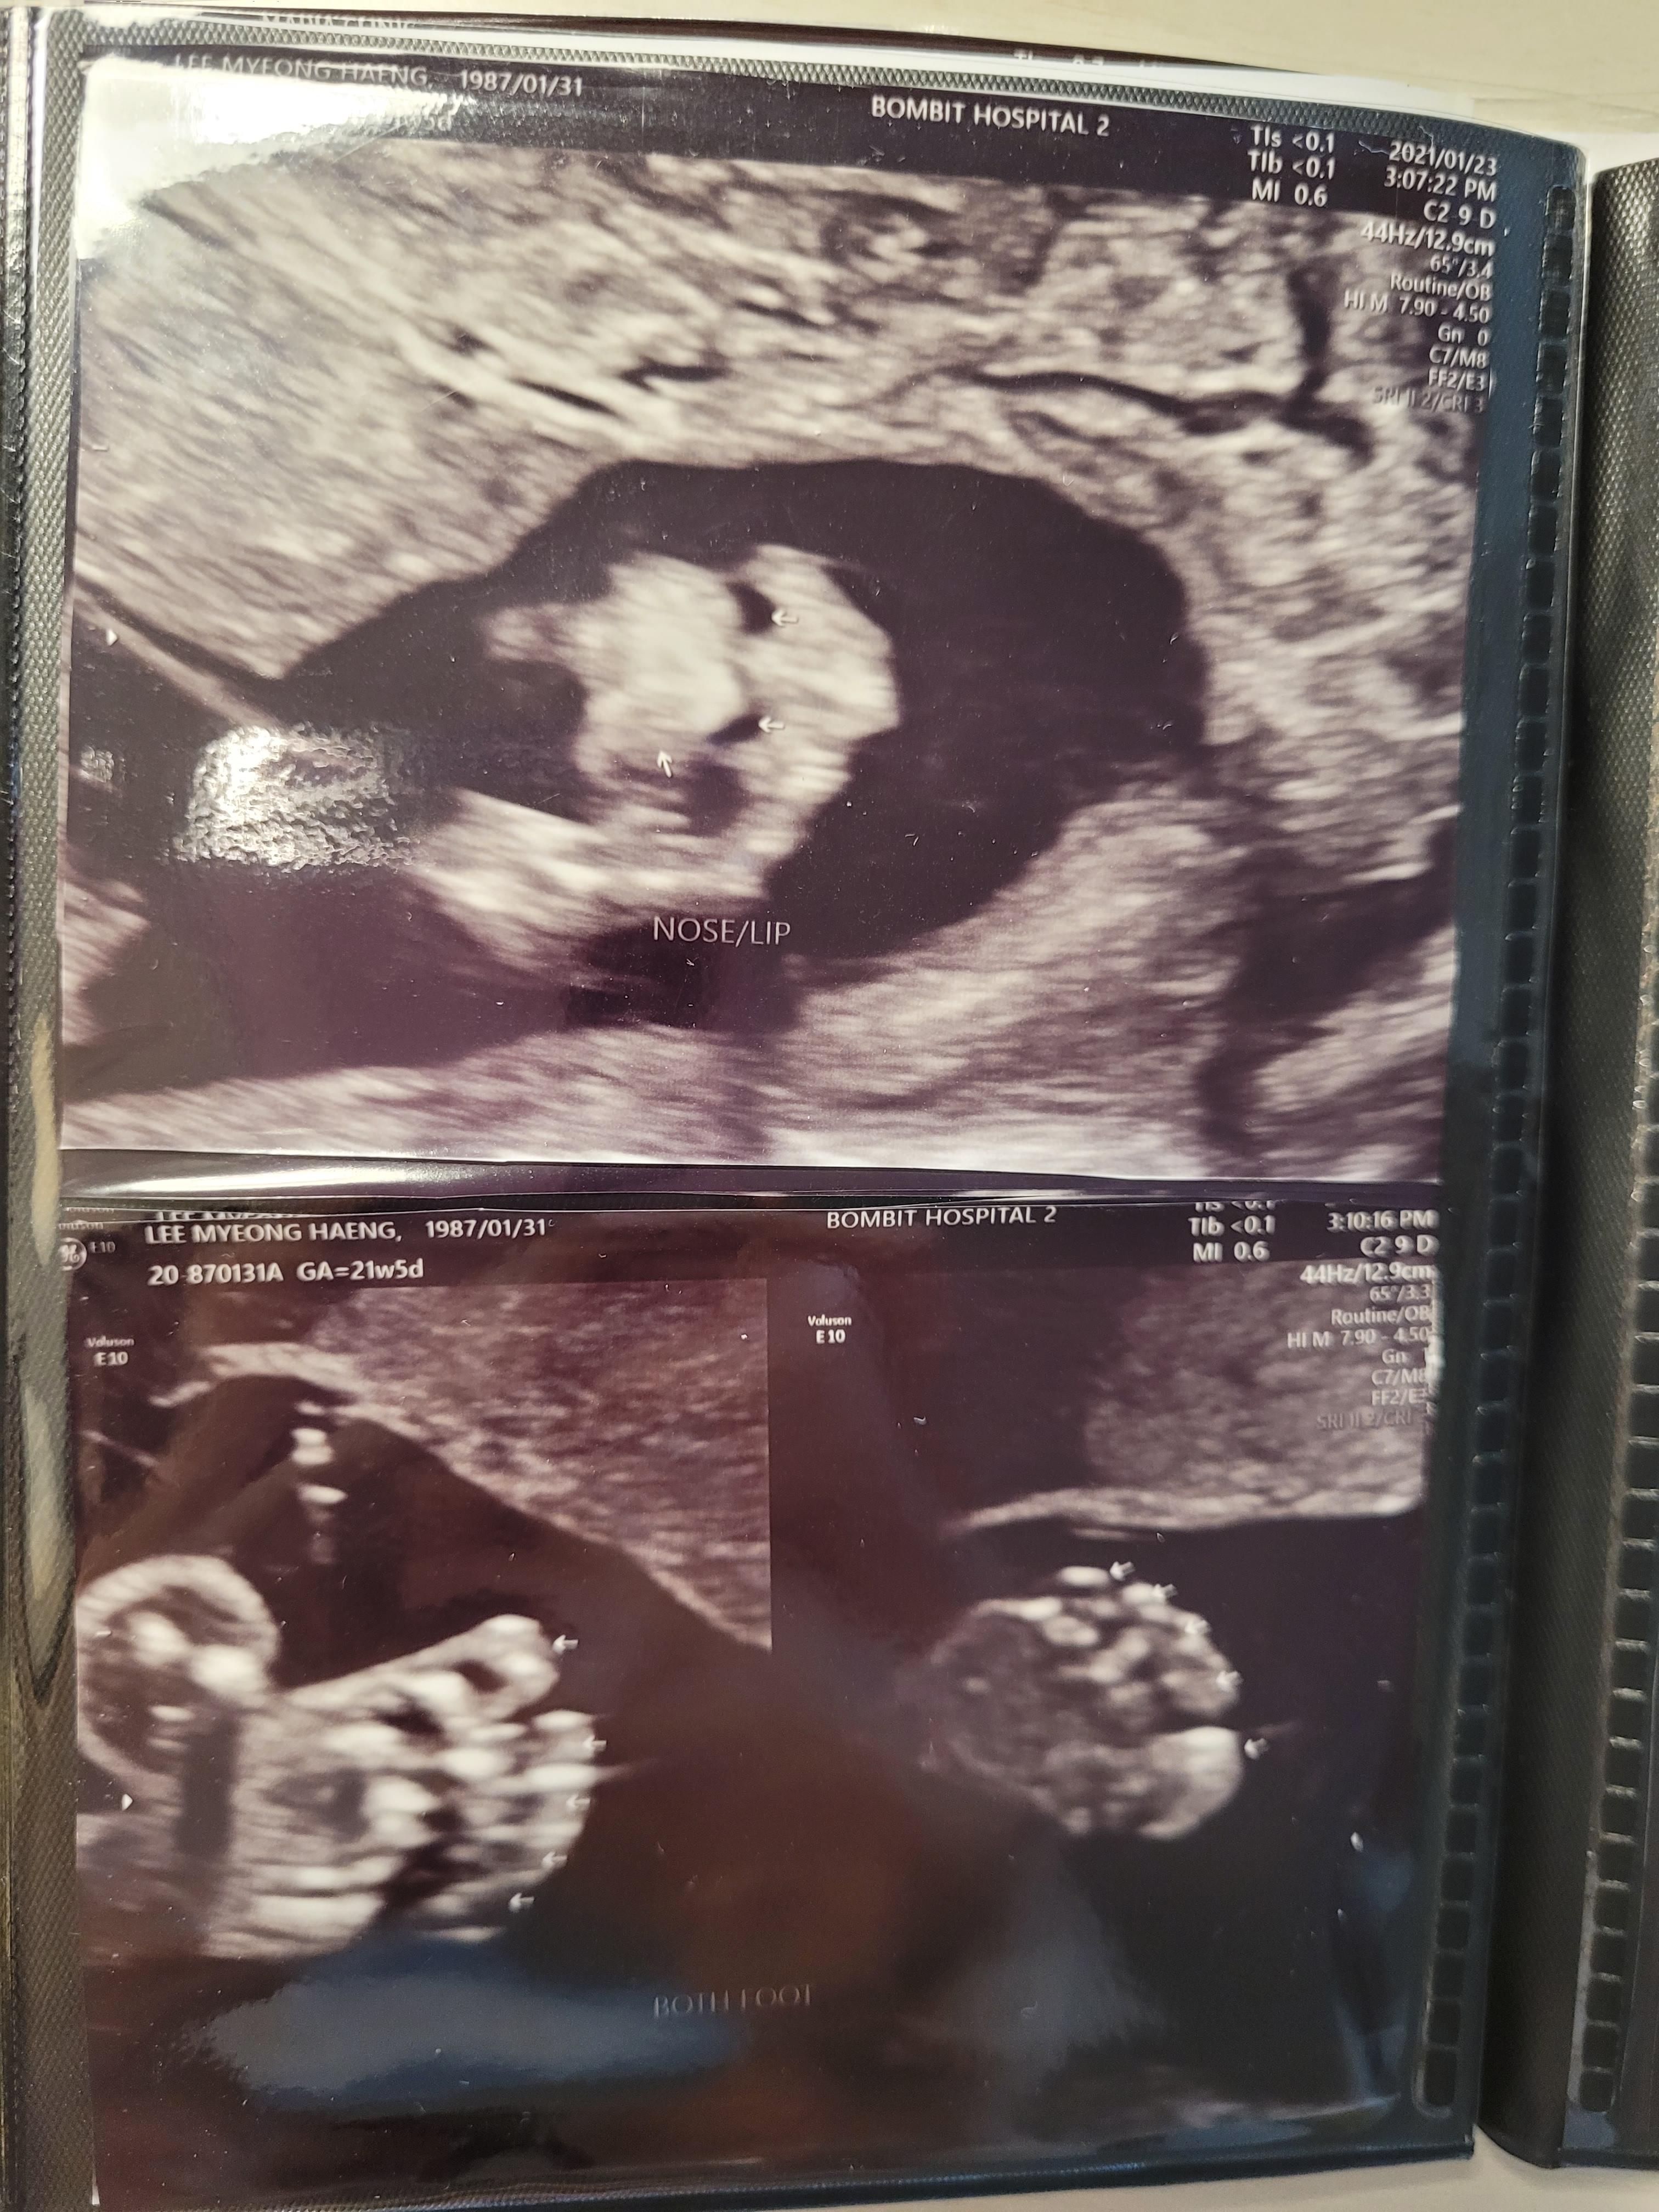

머리부터 시작해서 발끝까지 정말 꼼꼼하게 봐주십니다.

손발, 눈코입은 물론이고요. 뇌초음파, 동맥 등등 혈관, 양수량, 척추 등등

손가락 발가락 5개 체크하는데 은근히 떨리는 마음..ㅎㅎ

행복이는 아무이상없이 무럭무럭 잘 자라고있네요.

사진도 엄청 많이 뽑아주셨어요.